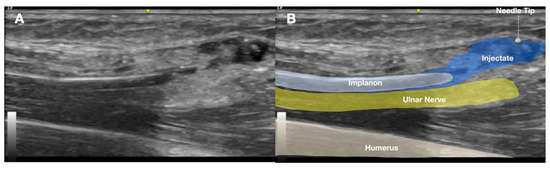

2.1. Prior Imaging Included Radiography (Figure 3), Which Confirmed the Implant’s Location, and Ultrasound (Figure 4), Which Demonstrated Its Proximity to the Ulnar Nerve